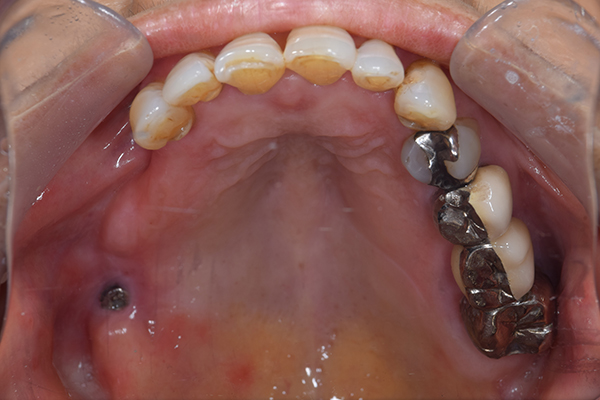

ケース2(自費の総入れ歯と部分入れ歯)

上下の入れ歯が外れやすくなったということでいらっしゃいました。 顎の骨はしっかりしていましたので、精密な型取りさえすればしっかりした入れ歯がつくれると思いました。 また下には6本歯が残っていましたが、虫歯になっている歯もありました。 かぶせ物のなかで大きな虫歯があった歯があり、1本だけ残せない状態でした。

上の入れ歯は確かに吸着は甘くなっていました。 また下の入れ歯はバネの一部が壊れており、安定感がなくなっていました。

精密な型取りの後、噛み合わせのチェックをしていきました。 かぶせ物も同時に作っていきました。

歯を並べた後、かぶせ物のフレーム作ってもらいました。先に歯を並べて理想の位置を決めておくことが大切です。

完成した入れ歯とかぶせ物です。 入れ歯への寛容度が高い患者様でしたので、 金属は使用せず、プラスチックのみで上は仕上げました。 下顎も歯は1本減ってしまいましたが、しっかり 入れ歯が維持できる様な構造にしました。

お口の中に入れた状態です。 見た目も最初とほとんど変わることなく作成できました。 維持や吸着に関しても問題ないようでした。

年齢 80歳・女性

主訴 上下の入れ歯が外れやすくなった

治療期間 3ヶ月

治療費 .メタルボンドクラウン:550,000円

.義歯:990,000円(税込、上下)

治療方針 長年使ってきた義歯の人工歯が磨耗し、臼歯部での咬合がすくなくなり、入れ歯の安定も悪くなり、あたりどころが悪くなって痛みが出ている。 そのため、入れ歯を上下作りかえる必要がある。

治療内容 過去に治療を行ったことのある歯が再度虫歯になってしまっているところがあり、すでに残せない状態にまでなっていたため、歯を一本抜歯した。 その後、かぶせ物と入れ歯を同時に作成していった。

特記事項 歯を抜いた後は、2〜3ヶ月歯ぐきの回復を待ってから入れ歯を作るため、待機期間があります。その間、古い入れ歯を調整しながらそのまま使うか、新し物をつくっておく必要があります。ただし、入れ歯は保険治療で作成する場合、6ヶ月は新しいものが作れないという決まりがあるので保険で全て作りたい場合は注意が必要です。